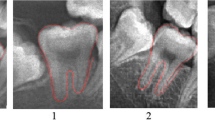

Using a large radiological database of 3605 orthopantomograms (1734 females and 1871 males) of healthy French patients aged between 2 and 24 years, seven left permanent mandibular teeth and the 4 third molars were assessed using Demirjian’s stages. Dental age estimation was then performed using Demirjian’s reference method and various ML regression methods. Two analyses were performed: with the 7 left mandibular teeth without third molars for the under 16 age group and with the third molars for the entire study population. The different methods were compared using mean error, mean absolute error, root mean square error as metrics, and the Bland-Altman graph.

Demirjian A, Goldstein H, Tanner JM (1973) A new system of dental age assessment. Hum Biol 45:211–227

Demirjian A, Goldstein H (1976) New systems for dental maturity based on seven and four teeth. Ann Hum Biol 3:411–421. https://doi.org/10.1080/03014467600001671